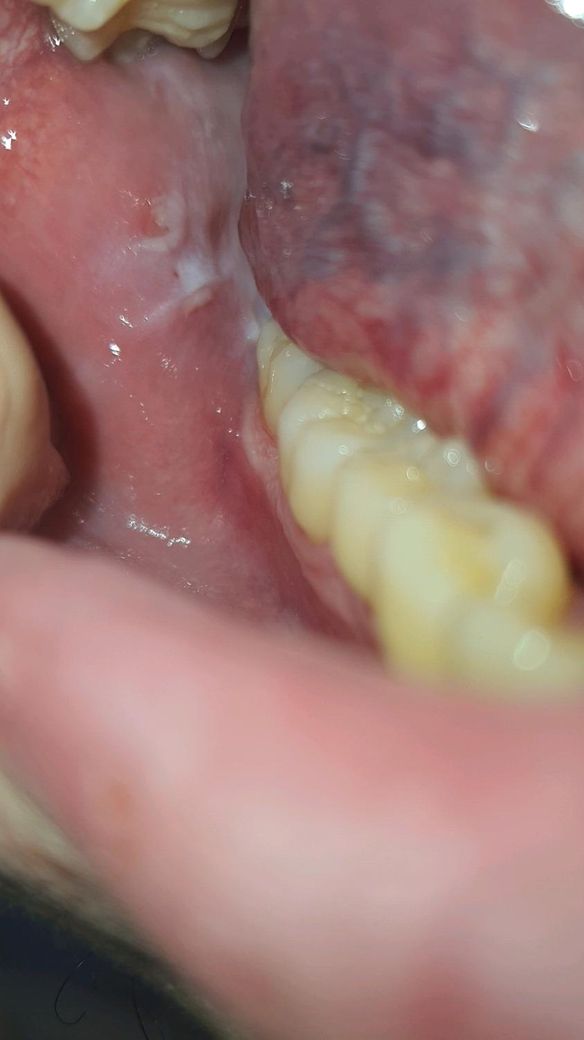

입안쪽 살이(어금니쪽) 하얀데 정상인가요?

안녕하세요 몇일전에 입안쪽 살이 너무 흰색인거같아서 혹시뭐 구강암이나 이런거 일거같아서 질문 올립니다 사진은 왼쪽이랑 오른쪽 어금니쪽 사진인데 왜이런걸까요.. 사랑니를 안빼긴했는데 그거때문일까요?

안녕하세요 몇일전에 입안쪽 살이 너무 흰색인거같아서 혹시뭐 구강암이나 이런거 일거같아서 질문 올립니다 사진은 왼쪽이랑 오른쪽 어금니쪽 사진인데 왜이런걸까요.. 사랑니를 안빼긴했는데 그거때문일까요 -> 암은 아닙니다 사랑니가 염증을 유발했을 수 있습니다

저부위는 위쪽 치아에 자극을 받아서 잇몸이 그런거 같습니다. 사랑니떄문에 잇몸이 튀어나와서 그런거 같으니 불편하시면 발치를 하시는게 좋을것같습니다.